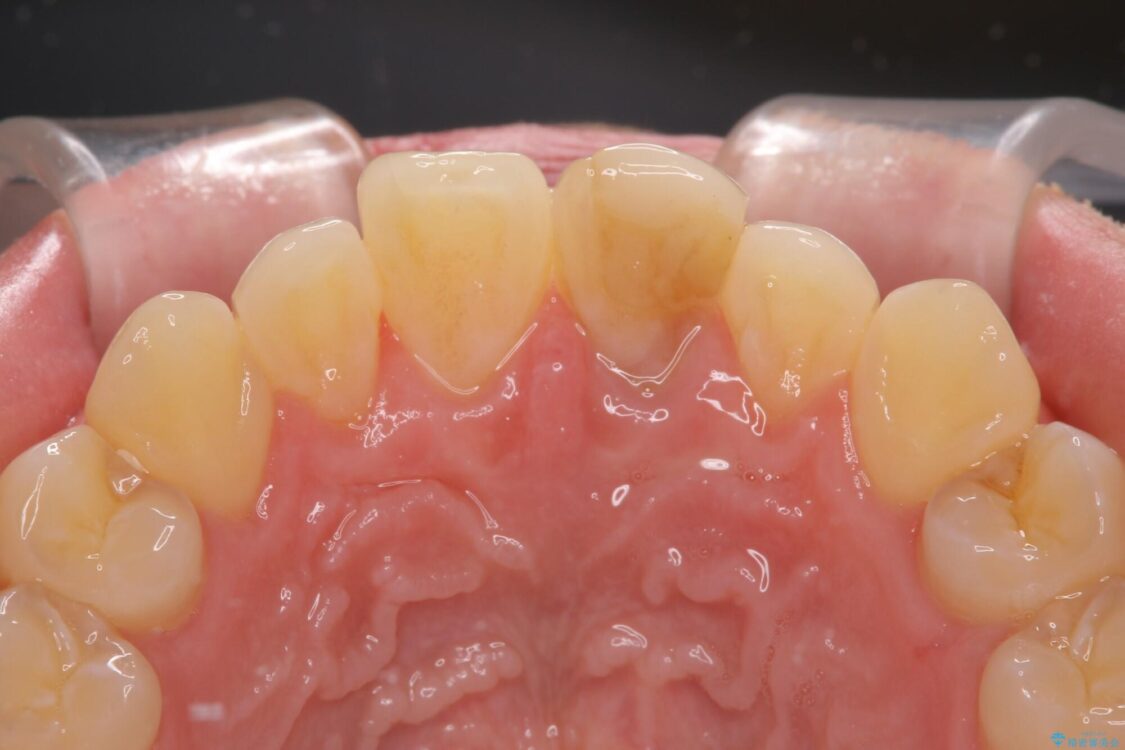

神経を取り除いたことで変色した前歯を気にして来院された患者様です。

神経を取り除いた歯は時間とともに変色してきます。

クリーニングやホワイトニングでは改善できないため、オールセラミッククラウンなどによる補綴治療が必要となります。

治療後

• 変色した前歯をオールセラミッククラウンに 治療後画像